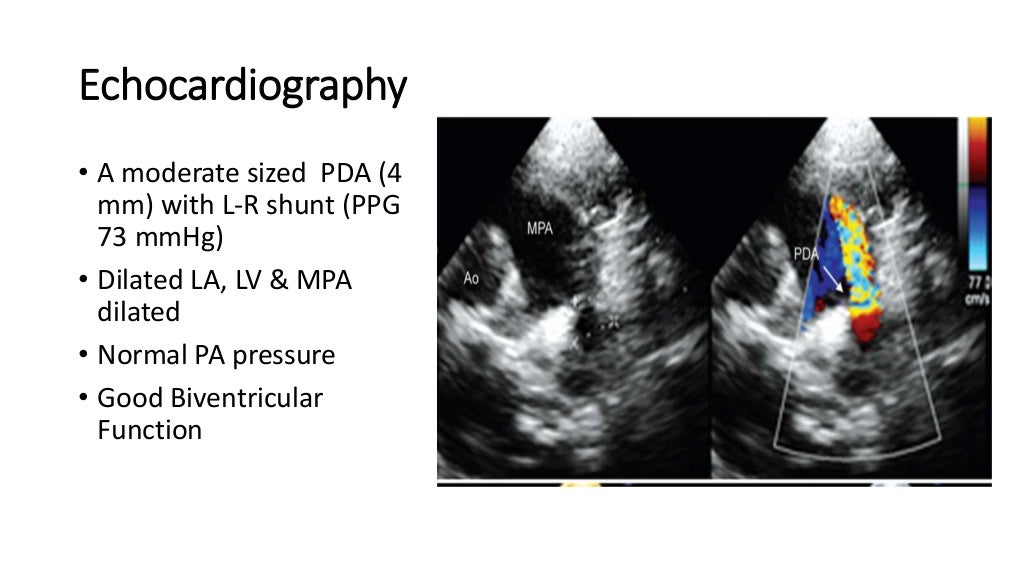

PDA Presentation Dr. Gaurav Agrawal Pda Case Presentation Patent ductus arteriosus (pda) is a congenital heart defect in which the ductus arteriosus, a vascular structure between the pulmonary. Patent ductus arteriosus (pda) accounts for approximately 5% to 10% of all congenital heart diseases. Ductal patency is a complication of extreme preterm birth [1]. Investigations confirmed moderate patent ductus arteriosus (pda) with heart failure and pneumonia. The patent ductus. Pda Case Presentation.